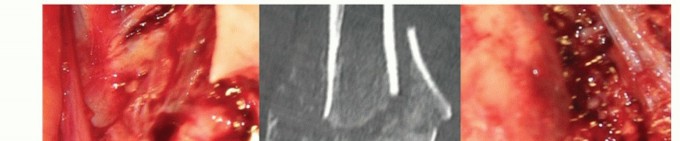

The ulnar canal preparation commences with removal of the tip of the olecranon. The intramedullary canal is entered at the base of the coronoid (TECH FIG 4C,D).

The entry point is enlarged toward the coronoid with a burr to allow easier component insertion without cortical abutment, which leads to malalignment (TECH FIG 4E).

During intramedullary preparation, the broaches must parallel the subcutaneous border of the ulna. This ensures that the track of insertion of the ulna parallels the intramedullary canal. This may require removal of bone from the greater sigmoid notch of the ulna.

The tip of the coronoid is removed to avoid impingement during terminal flexion (TECH FIG 4F,G).

The radial head does not need to be resected if there is no disease of the proximal radioulnar joint (TECH FIG 4H).

TECH FIG 4 • (continued) B. The posterior flat surface of the humeral shaft is identified and the component is aligned. C,D. Ulnar canal preparation is commenced by opening the canal at the base of the coronoid process with a drill or burr. E. The trajectory of the ulnar component (black ring) is prepared by rasping the entry track posteriorly into the ulna with a rasp or bone nibbler (gray crescent). F,G. The tip of the coronoid should be resected sufficiently to prevent abutment on the humeral flange during full flexion. Also shown are the resections of the olecranon and the entry point for the ulnar stem insertion. H. The partially resected radial head is used as a bone graft for incorporation behind the humeral flange.